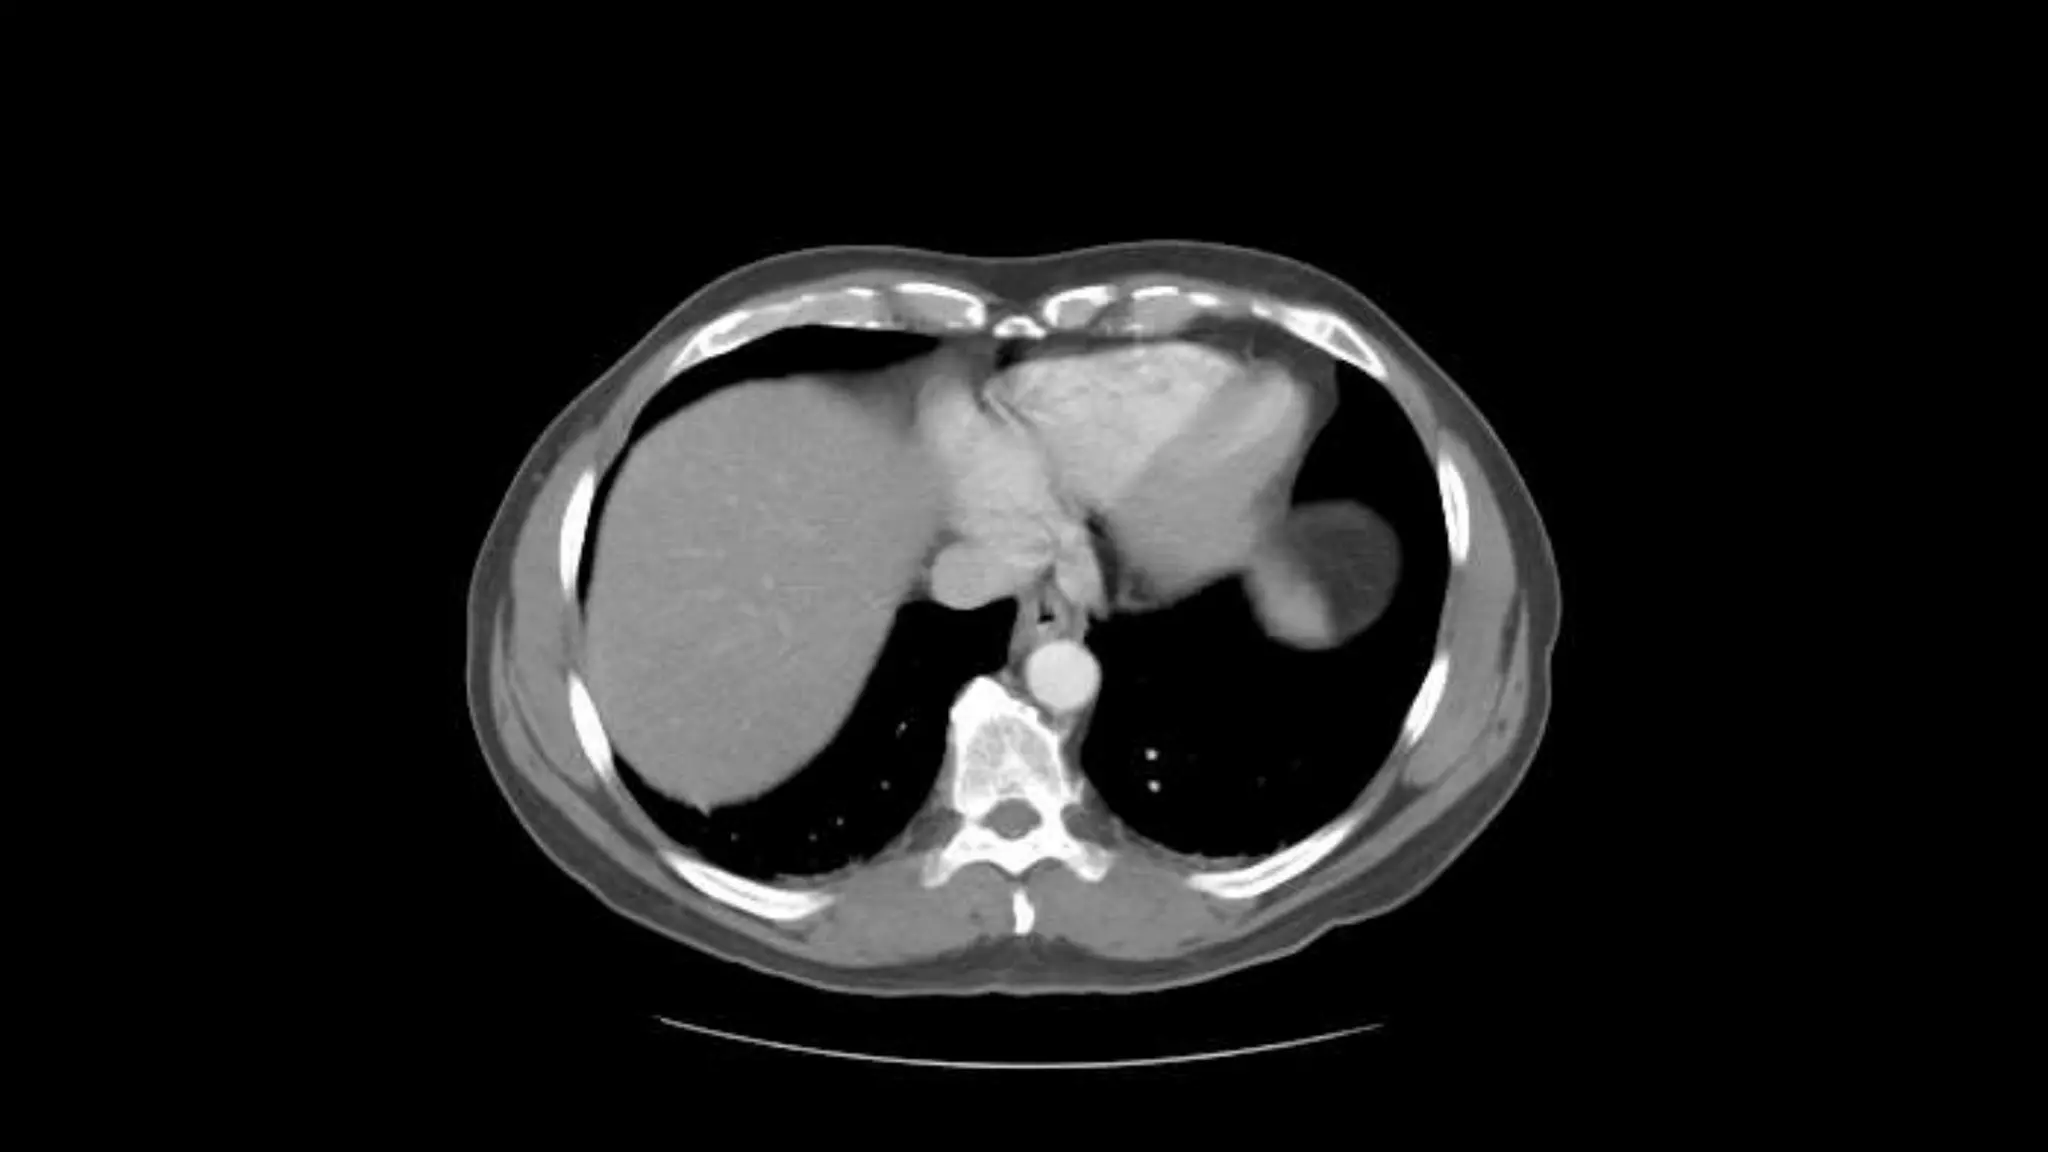

 In this sequence of images, we will label the abdominal vasculature.

The CT images are 5mm slices with soft tissue window settings. IV

 IMAGES ARE VIEWED AS LOOKING FROM THE FEET

RIGHT LEFT

Follow the IV contrast filled Aorta as we descend caudally. Branches and points

of interest will be noted.

This is an excellent image of the right, middle and left hepatic veins draining into the Inferior

Vena Cava. Don’t confuse this structure with the IVC, this is the esophagus at the level of the

Lower esophageal sphincter, page up and down to confirm this.

The outline of the Inferior Vena Cava is more

distinct in this image.